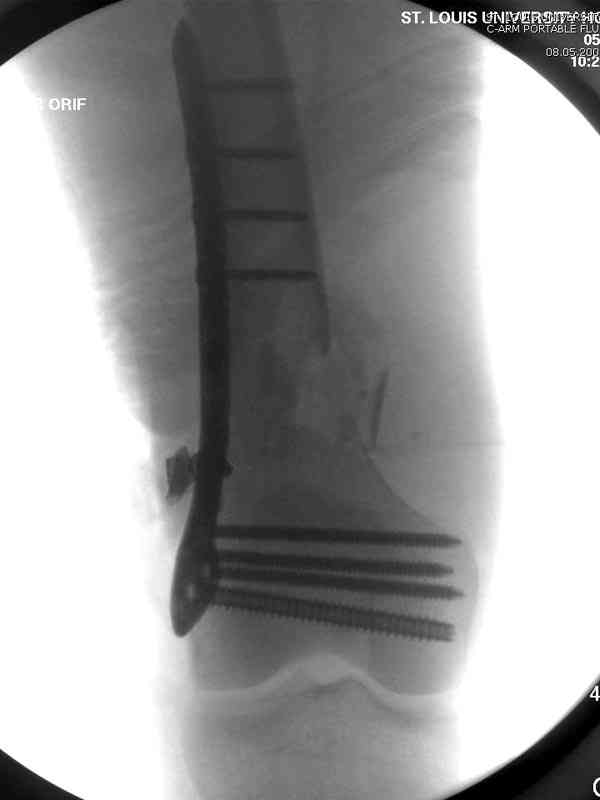

Доступ был латеральный, при вскрытии с задней

поверхности бедра обнаружили кровотечение. Поднятием давления на заранее установленном турникете на конечности проконтролировали кровотечение.

В данном случае мы не ставили осуществление гемостаза приоритетным, после 30 минут больной оставлен вызванному сосудистому хирургу со стабильной фиксацией бедра. Несмотря на выбранный передне-медиальный доступ, хирург произвел восстановление сосудистого повреждения.

Латерально пластину защитили ушиванием

илио-тибиального тракта, а медиальная сторона была ушита мышцей, и все раны закрыли ваккумированием (VAC)